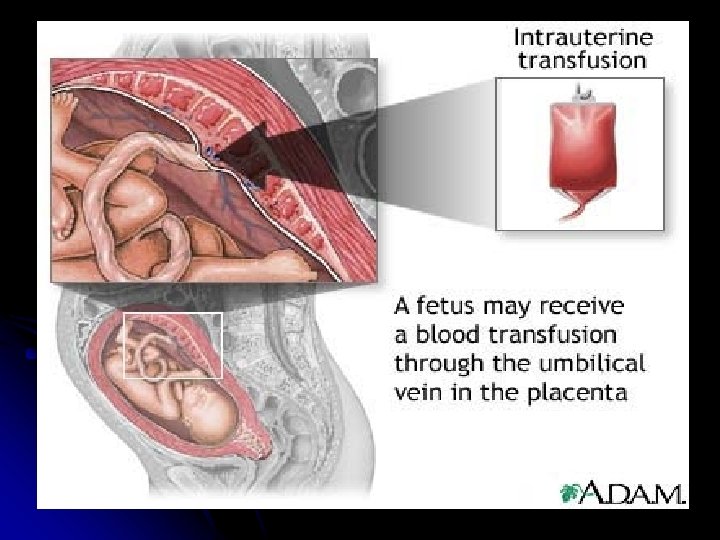

Intrauterine Transfusion -The goal is to transfuse fresh group O, Rhnegative packed RBCs. -The blood for transfusion require; -routine blood screening. -irradiation. - washing and processing through leukocytepoor filter. - screen for cytomegalovirus.

-The procedure ; -The repeated transfusion are generally scheduled at 1 to 3 week interval. -The final transfusion is typically performed at 34 to 35 weeks’ gestation. - the overall survival rate following intrauterine transfusion is about 85%